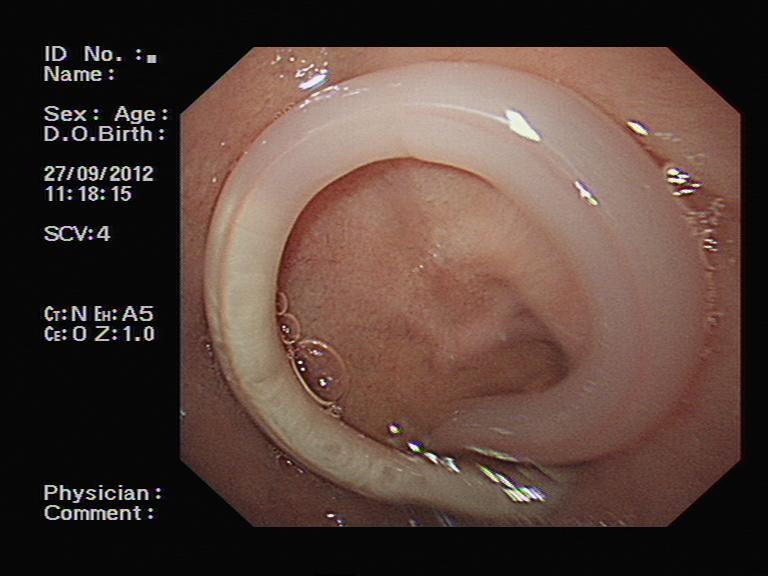

胃镜检查证实了胃角部位的一处不大的溃疡,我们再次进行了活检。不过,意想不到的是,当检查医师进镜至十二指肠时,吃惊地发现十二指肠球部有一个正在蠕动的白色圆柱状物体,这是什么呢?原来是一条蛔虫,头端还在十二指肠降部,尾端留在了球部。见状,蔺武主任医师反复尝试,最终用圈套器取出了蛔虫。患者家属很高兴,因为找到了腹痛的原因,那么,事情结束了吗?检查之后病理很快回报:患者的胃溃疡活检标本中存在局部癌变,该患者的胃角溃疡为早期胃癌。

十二指肠球部可见蛔虫尾端